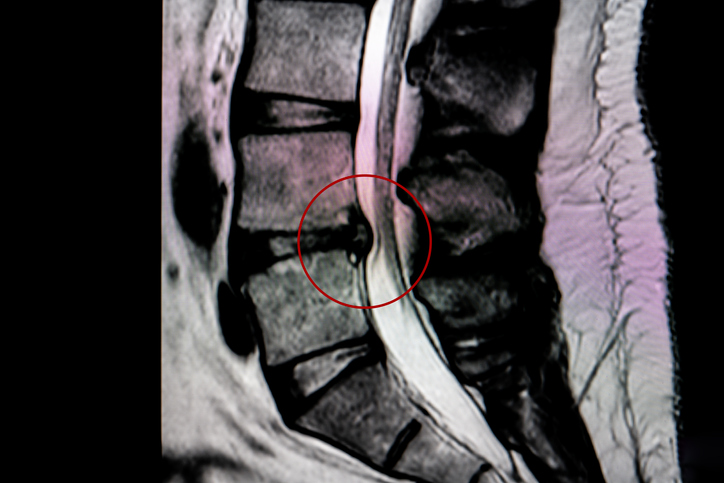

A spinal tumor is an abnormal mass of tissue within or surrounding the spinal cord and/or spinal column. During surgery, the spinal bones (laminae) are removed to access the spinal canal. The tissue-lined compartment that contains the spinal cord and nerves that are surrounded by spinal fluid is called the dura. The surgeon opens the dura to expose the spinal cord and nerves and remove the tumor. Then the dura is then sutured and closed.

Lumbar decompression surgery is a type of surgery used to treat compressed nerves in the lower (lumbar) spine. Surgery can improve symptoms such as persistent pain and numbness in the legs caused by pressure on the nerves in the spine.

Laminectomy is a type of surgery in which a surgeon removes part or all of the vertebral bone (lamina). This helps ease pressure on the spinal cord or the nerve roots that may be caused by injury, herniated disk, narrowing of the canal (spinal stenosis) or tumors.